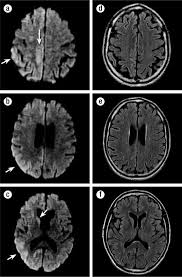

Variant Creutzfeldt Jakob Disease In A Patient With Heterozygosity At Prnp Codon 129 Nejm

Variant Creutzfeldt Jakob Disease In A Patient With Heterozygosity At Prnp Codon 129 Nejm from www.nejm.org